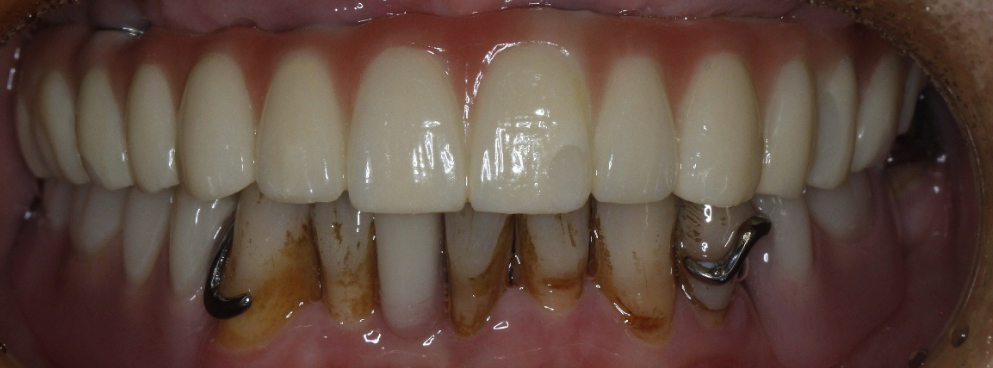

该患者就是因牙周病导致牙齿松动脱落,我们通过在半口牙槽骨上植入8颗种植体,然后在种植体上安装连桥牙冠,从而恢复半口牙齿的咀嚼功能和美观。相对于传统的种植修复方式缺一颗种一颗。4-8颗种植体的种植手术创伤相对较小,大大的减少了患者的疼痛感。

种植牙是当前缺牙修复的理想选择,但成功与否依赖医生技术、患者自身条件和术后维护。尽早修复缺牙,才能避免邻牙倾斜、咬合紊乱等问题,重获健康笑容